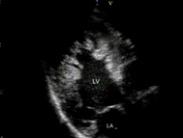

心室肌致密化不全治療

• 心室肌致密化不全

628健康網為您分享有關心室肌致密化不全的癥狀,心室肌致密化不全的治療方法,心室肌致密化不全的預防知識,心室肌致密化不...